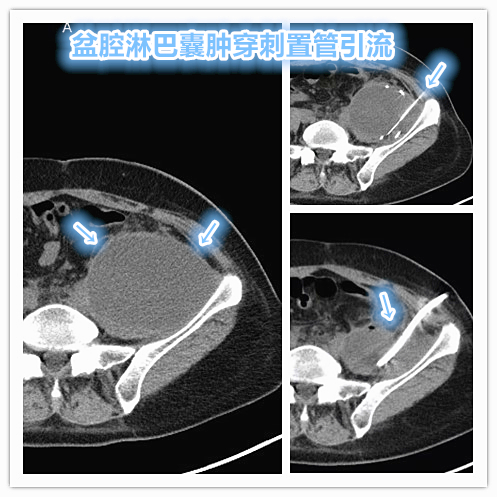

随后杨女士转诊至介入科,经评估考虑为复发、难治性盆腔淋巴囊肿,且已继发严重感染。随即安排CT引导下经皮穿刺盆腔囊肿置管引流,抗生素反复冲洗治疗,经治疗后患者症状即刻缓解。后续联合抗感染治疗,待囊液充分引流后予以硬化治疗,闭塞囊壁。CT介入硬化治疗妇科术后盆腔淋巴囊肿

宫颈癌切除术中的淋巴结清扫及术后辅助放疗是导致术后出现盆腔淋巴囊肿的常见原因。经皮穿刺抽液治疗盆腔淋巴囊肿复发率较高,单纯置管引流成功率为79%~87%,复发率高达30%。因此,对于复发难治性盆腔淋巴囊肿需充分引流后行硬化闭塞治疗,必要时需行淋巴管栓塞术以减低术后复发率。复发/难治性盆腔淋巴囊肿的介入淋巴管栓塞治疗